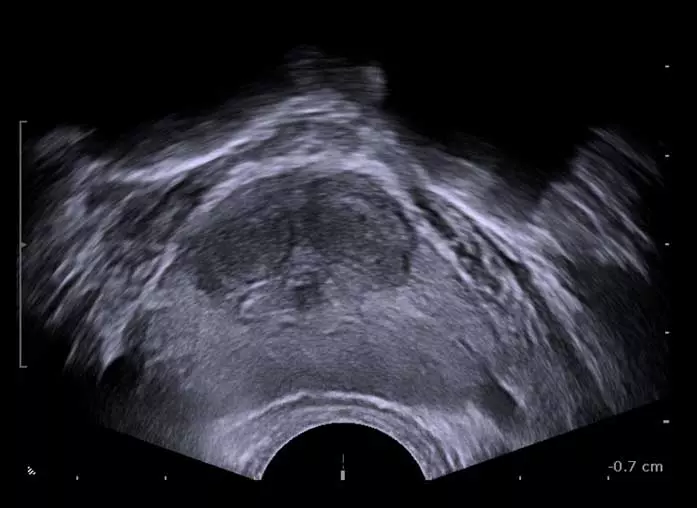

진료실에서 실제로 초음파 영상을 제시하면 환자들도 “가운데 막힌 게 보인다”라며 바로 이해한다. 특히 가운데에 잠자리 눈처럼 동그랗게 알맹이가 보이고 이행대가 바깥과 확연히 구분돼 보이면, 소변 길이 막혀 있을 가능성이 높다. 그래서 크기가 작아도 소변을 약하게 보는 환자가 있고, 반대로 크기가 크더라도 의외로 소변을 잘 보는 차이가 생긴다.